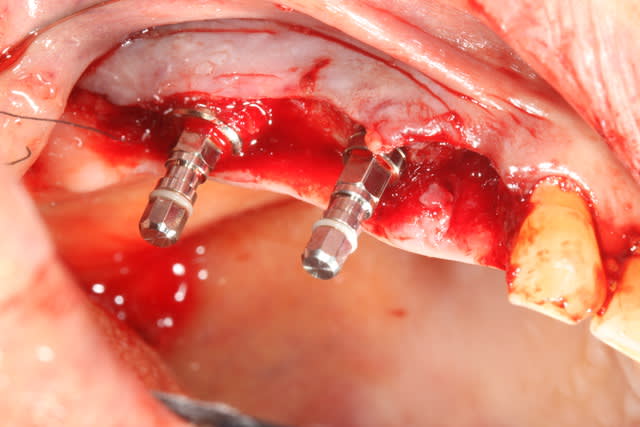

voici mon premier cas d'Extraction implantation Immediate...

1/as tu place une membrane pour ta rog?

2/ pourquoi le faire en un temps? Le risque d'echec de la rog est majore dans cette approche je pense?

Justement cartman...

J'avais prévu en amont; bio oss et membrane.

En examinant la paroi vestibulaire de l’alvéole après extraction...j'ai pensé que la résorption faisant l'option implantaire serait plus compliquée par la suite. J'ai donc posé l'implant en 24;

A posteriori je me dit que j'aurai du poser la membrane autour de l'implant pour éviter la compétition cellulaire et optimiser mon comblement.

On va dire que j'ai été ptit bras sur ce coup.

bravo ! Pour la 24, la prochaine fois commence avec un trépan dans le septum:

tes forets suivant ne seront plus déviés et tu aura un peu d'os à mélanger au Bio-Oss

Ici, pas besoins de membrane car ton défaut osseux est à 4 parois

dommage que tu sois si timide pour la longueur des implants, y'avait de quoi mettre un peu plus long et faire une mise en esthétique immédiate